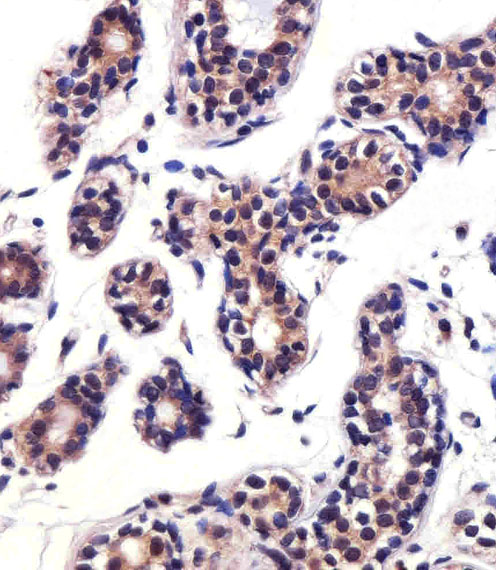

Immunohistochemical analysis of paraffin-embedded H.breast section using PTK2B Antibody (C-term)( AMR09636G). AMR09636G was diluted at 1:25 dilution. A peroxidase-conjugated goat anti-rabbit IgG at 1:400 dilution was used as the secondary antibody, followed by DAB staining.